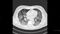

新型コロナ感染症の初期症状の一つに、肺炎が進行し、身体に必要な酸素を十分に取り込めない状態であるのに、なぜか自覚症状がなく、苦しくないことがあることが指摘されています。これをハッピー・ハイポキシア(=幸せな低酸素症)またはサイレント・ハイポキシア(=沈黙の低酸素症)といいますが、ハッピー・ハイポキシアの状態で安心していると、急激に呼吸状態が悪化して、すぐさま人工呼吸を行わないと命が危ない状態になることがあるのです。これには、ハッピー・ハイポキシアの間、自覚症状はないが、実は自ら激しく息を吸ったり吐いたりしており、それによって肺がさらに痛んでしまうこと(自発呼吸誘発性肺傷害 第13回/参照)が関与しているのではないかと言われています。4月に自宅待機中にハッピー・ハイポキシアになった患者を、緊急に収容し何とか一命を取り留めました(第2回参照)。早期入院して看護師が呼吸モニタリングしていれば、酸素の投与を早めに行え、自発呼吸による肺障害を軽減することができます。